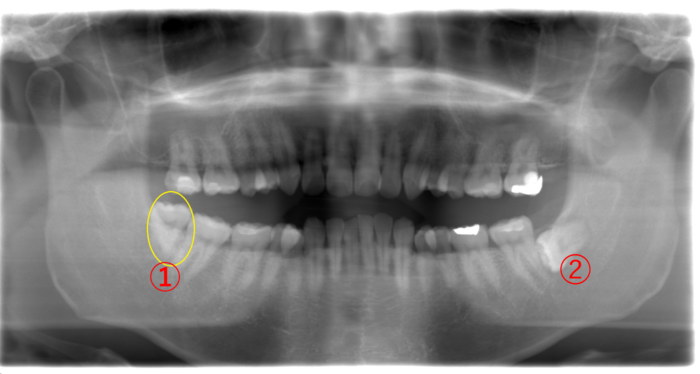

| 年齢・性別 | 26歳・男性 |

|---|---|

| 主訴 | 左上の親知らず(画像④)が痛くて我慢ができない。どちらかというと鋭い痛みがある。 |

| 歯ブラシ | 奥まで磨けていない。お口の中に汚れが結構残っている。 このままでは親知らずだけではなく、他の歯が虫歯になる可能性が高い。 |

親知らずが生えることによる痛みとは異なる「鋭い痛み」の原因究明のため、まずはレントゲンを撮影しました。

画像④の親知らずに大きな黒い虫歯の影が見えます。虫歯になると歯が溶けて柔らかくなるので、レントゲンには黒く写ります。

また、1番奥にある親知らずまで歯ブラシが届かずに、気付いたら虫歯が大きくなっていたことが予想されます。

虫歯の痛みが強い時に親知らずを抜こうとしても麻酔が効きにくいことが予想され、患者さまの負担を考えると無理に親知らずを抜かないことも選択肢のひとつになります。

そこで、この患者さまには、今すぐに親知らずを抜くのではなく、まずは虫歯の痛みをとる治療を優先させて、虫歯の痛みが無くなってから親知らずを抜きましょうと説明しました。

画像④の親知らずを抜いた場合、下の➁の親知らずを抜かずに放置すると上に伸びて来て、かみ合わせの邪魔をすることがあります。

そのため、上下同時に親知らずを抜くか、④の親知らずを抜いてから➁の親知らずを抜くか、どちらかになります。また、右上④の親知らずがないため、②と④の抜歯後、①の親知らずを抜きます。

上下どちらかの親知らずを抜歯した場合、その対合する親知らずが生えていたら抜歯し、片側の親知らずを抜歯した場合は、もう片側上下にある親知らずを順次抜くことを検討するとその後のトラブルは少ないと思います。